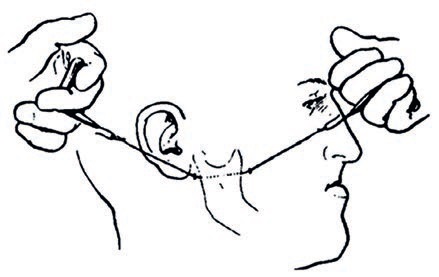

Streszczenie: Agenezja bocznych siekaczy szczęki jest najczęściej występującą anomalią rozwojową zębów. Postępowanie w przypadku braku siekacza bocznego polega na zamknięciu luki z wykorzystaniem kła jako namiastki siekacza albo na ortodontycznym utworzeniu przestrzeni dla uzupełnienia protetycznego. Uważa się, że – ponieważ luka występuje w obszarze estetycznym – odpowiednie podejście do potrzeb pacjenta wymaga starannej diagnostyki i planu leczenia. Taki problem jest dużym wyzwaniem dla ortodontów, protetyków i stomatologów ogólnych. Niniejsze doniesienie kazuistyczne opisuje postępowanie ortodontyczne u 22-letniej dorosłej pacjentki z brakiem górnego lewego bocznego siekacza i widoczną luką w odcinku przednim łuku zębowego, u której dokonano zamknięcia luki za pomocą lateralizacji kła i ukształtowano go w taki sposób, by stanowił namiastkę siekacza. Jednak w celu osiągnięcia optymalnej estetyki i poprawy zgryzu kluczowe są pewne modyfikacje w mechanice leczenia. Zamknięcie luki z wykorzystaniem lateralizacji kła wydaje się mniej inwazyjne, leczenie można zakończyć w stosunkowo krótkim czasie, a kolejny czynnik przemawiający na korzyść tej opcji to adaptacja przemieszczonego zęba do zmian, jakie z biegiem lat zachodzą w obrębie twarzy, bez konieczności uzupełnień protetycznych.